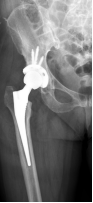

近日,一位久病缠身、下地活动极其困难的患者在我校附属南海医院做了人工全髋关节置换术,术后第二天患者就已下地站立、行走,且患肢短缩完全得到纠正,髋关节功能恢复良好。病人恢复如此迅速,出乎患者及其家属们的预料,该手术也成为3D打印在骨科和人工关节精准手术领域中的应用典范。

回忆起患者刚来南海医院脊柱关节外科时的情形,科室主任张毅介绍,患者股骨头严重坏死、脱位,且髋臼有一大块缺损,患肢短缩超过2厘米、关节囊挛缩、明显畸形,患者病情重、病程长、髋关节活动严重受限。如果想要从根本上解决患者病痛,提高患者的生活质量,必须行手术治疗。但这将是一例高难度、操作复杂的髋关节置换术病例。

主任张毅带领南海医院骨科中心髋关节置换项目组成员迅速行动,经详细讨论达成共识,认为该患者人工髋关节置换手术难度主要在于髋臼侧骨缺损导致髋臼假体安放困难。

但传统X线、CT、MRI等检查在了解髋臼缺损方面不够全面、精准、直观,在手术方案确定和假体选择上都给医生出了难题。为此,大家决定借助“神器”3D打印技术,以1:1再现患者的病患髋关节,以便精准制定手术方案。与此同时,项目组成员迅速联系影像中心获取了患髋CT数据并使用MIMICS软件重建患髋三维图像并使用3D打印技术1:1再现患者的髋关节,根据髋关节模型,项目组再次详细致地讨论了手术方案,并在术前与患者及其家属通过3D模型直观的介绍患者的病变以及手术的方案,获得了患者及家属的理解和支持。

术前

术后

以往在人工髋关节置换手术前,医生只能根据术前X线片去判断髋臼骨缺损的大小和位置,对手术的帮助非常有限。3D打印的关节模型,就能帮助医生术前精确的了解和测量髋臼缺损的大小和位置、同时了解整个骨性髋臼臼壁、臼底的骨质厚度,为手术提供精准的术前设计,合适的假体选择,大大缩短手术时间,减少了手术并发症的发生。3D打印技术不仅可以术前为患者定制个体化的手术方案,而且还可以运用模型在体外进行“实战演练”,确保了人工髋关节精准置换。同时也可应用于外科教学,具有直观、全面、准确、可交互的特点,有效地缩短年轻医生的手术学习曲线,提高手术的成功率。做到了精细、精准,提高了复杂人工关节置换术的成功率、降低高难度人工关节置换术的失败率,实现了骨科在复杂的关节置换术上又一次技术突破。通过与患者的术前交流和沟通,使患者充分地理解接受手术,积极配合医生术后康复锻炼。